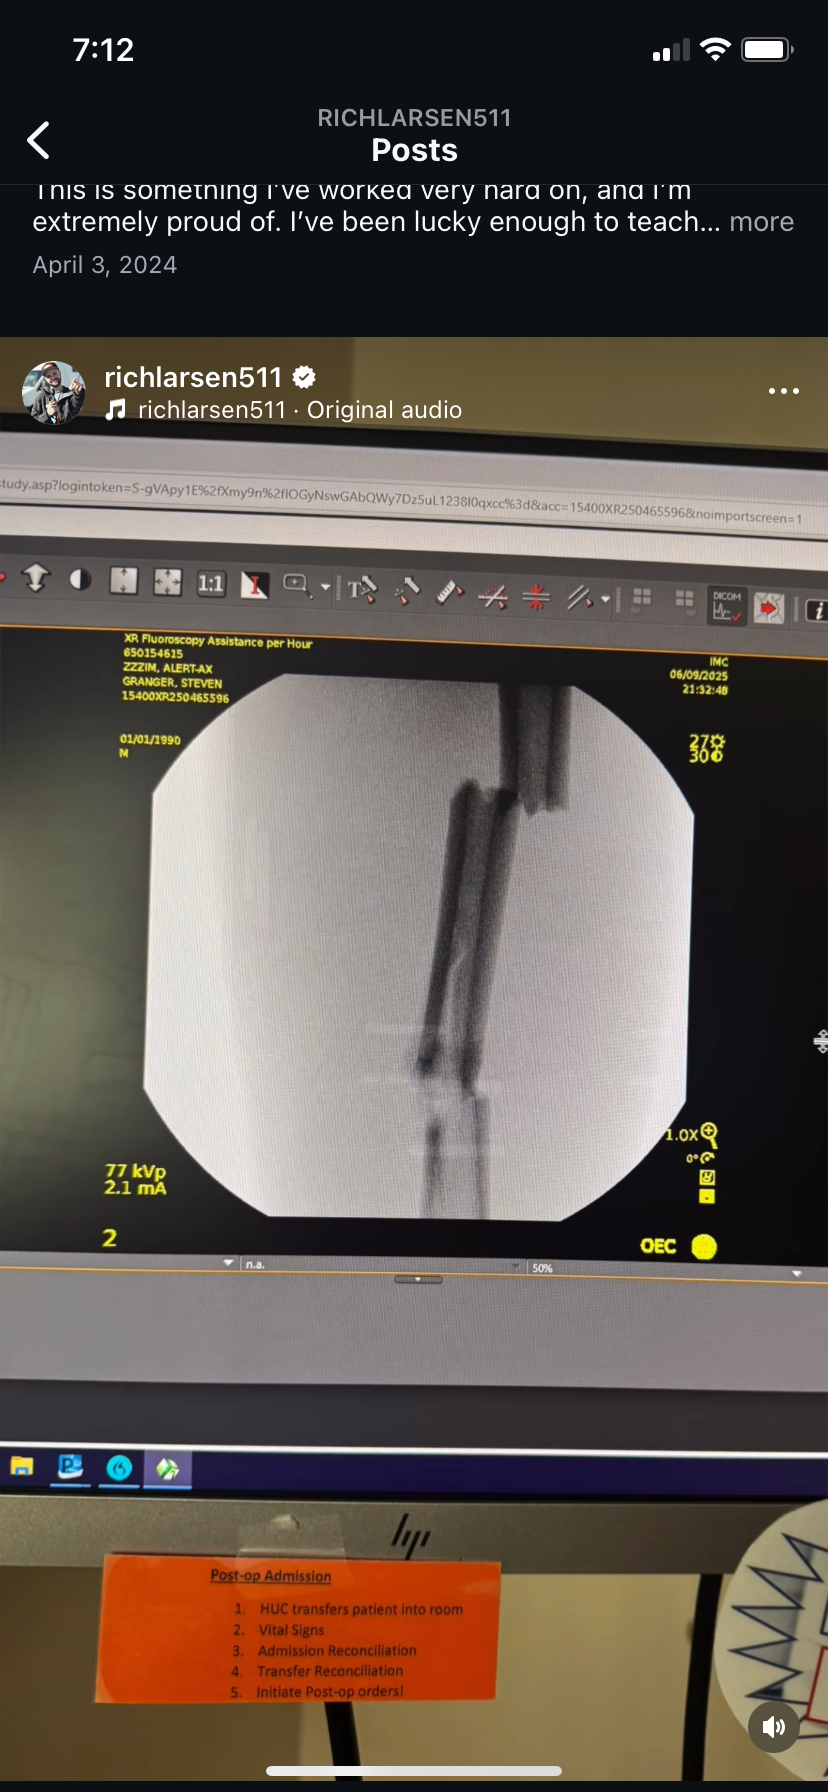

I'm reaching out to gather support for an outstanding individual, Rich Larsen. Last Monday, Rich experienced a serious accident that resulted in a broken femur, leaving him unable to work and facing a long recovery.